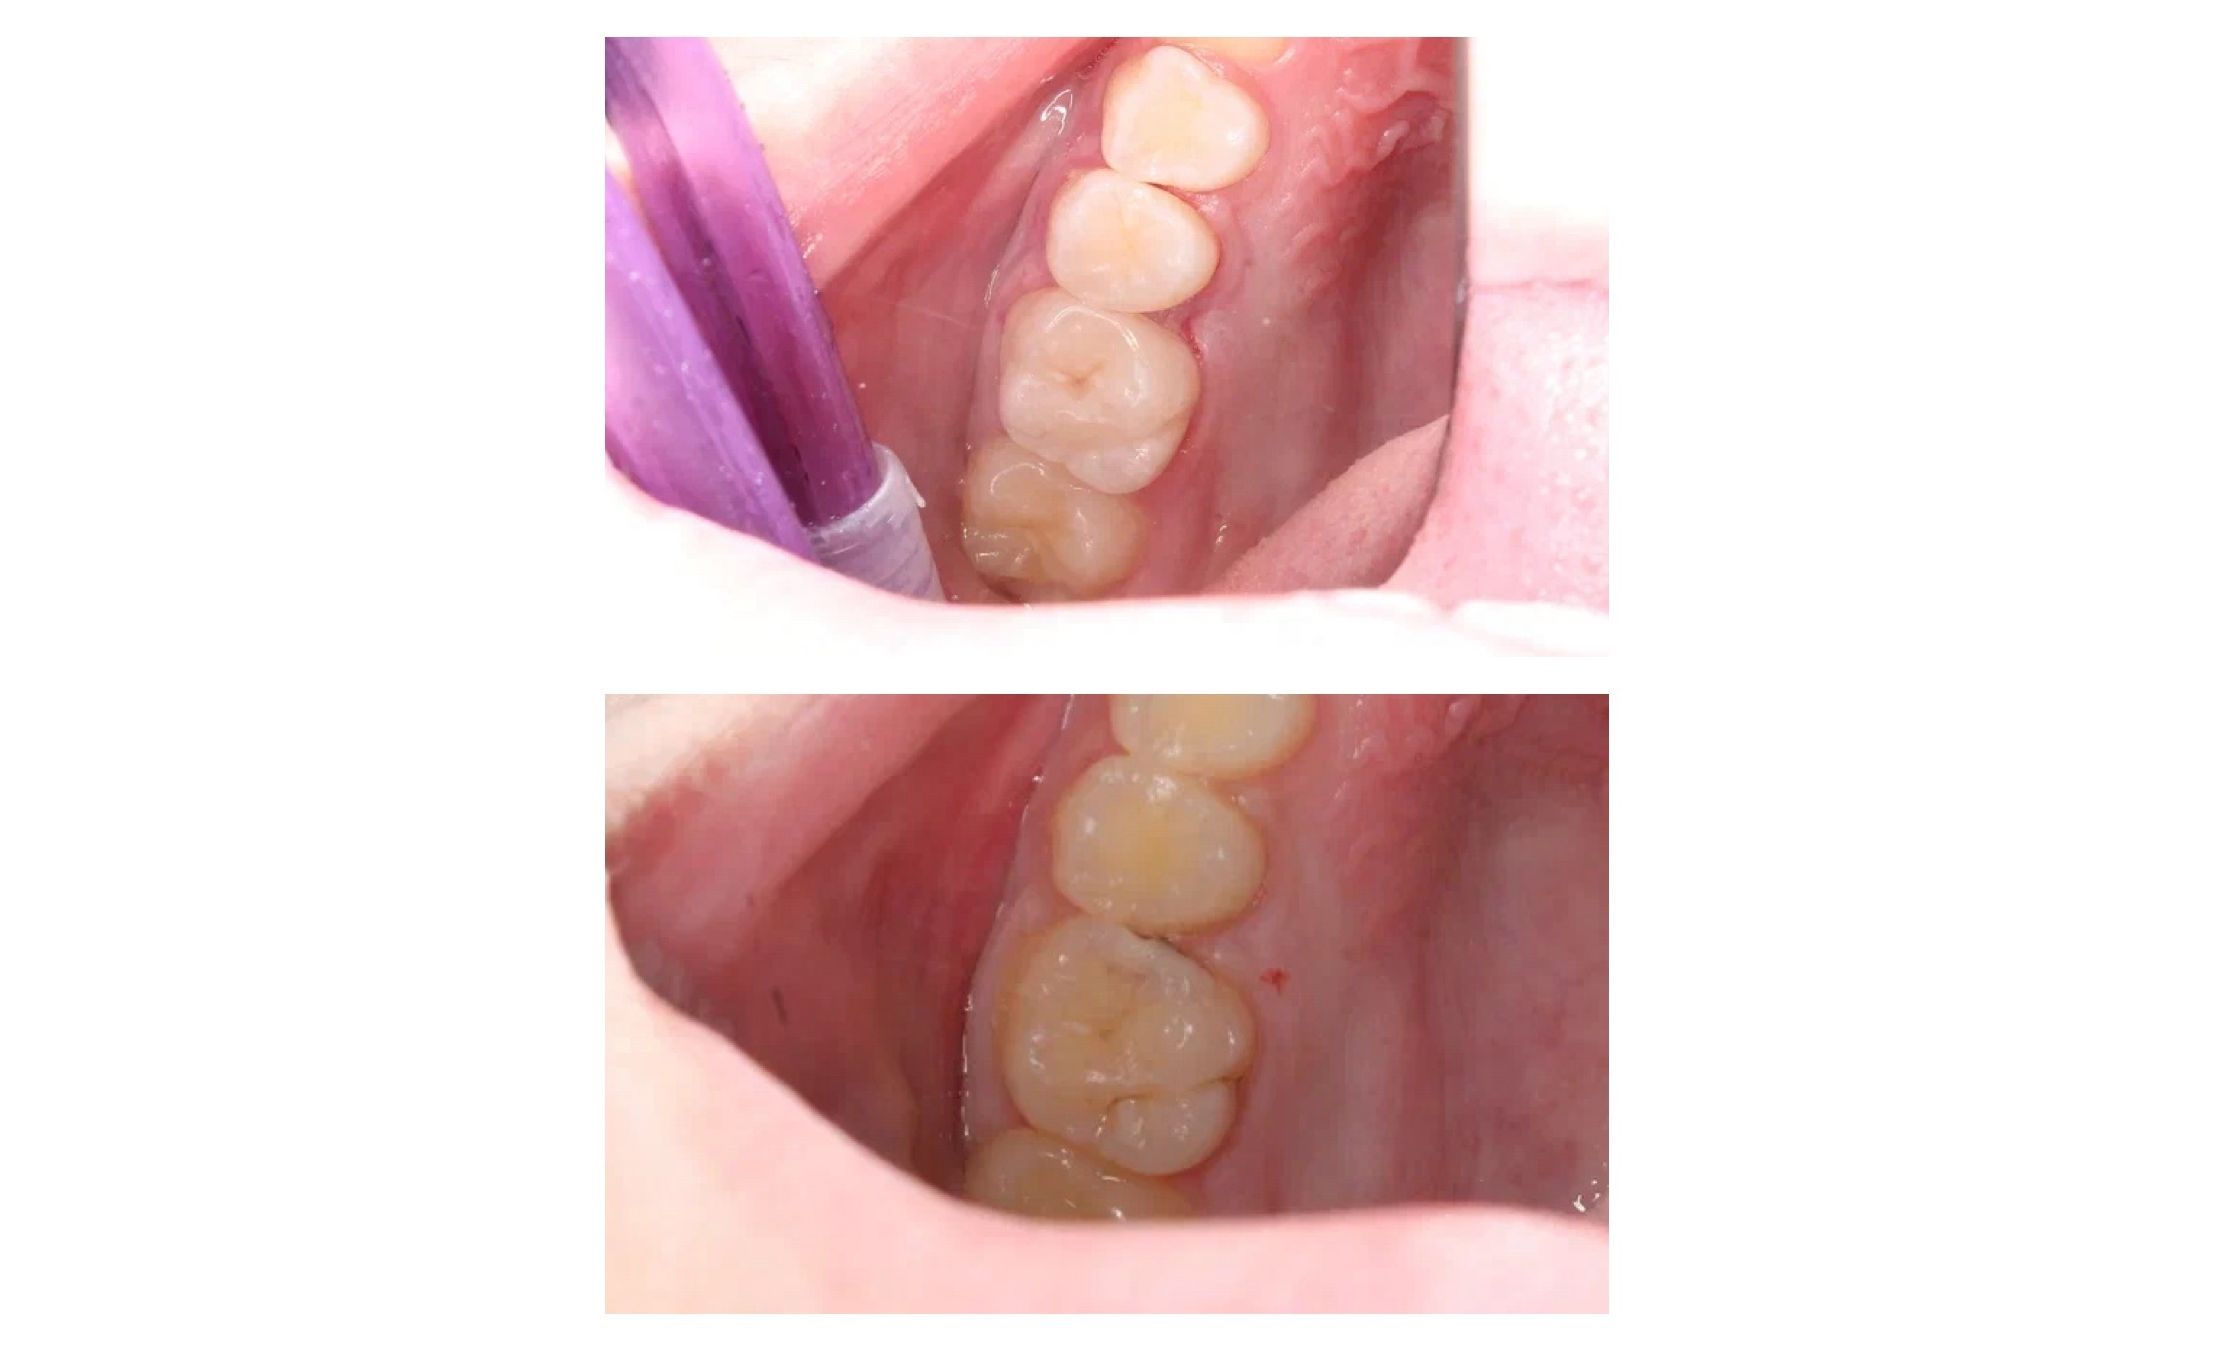

В карусели кейс врача стоматолога-терапевта Колиш Максима Петровича:

Пациент обратился с жалобами на застревание пищи между зубами, реакцию на сладкое и холодное.

При осмотре обнаружен контактный кариес на зубах 26, 25. Лечений в один визит. Восстановление функциональности композитной реставрацией.